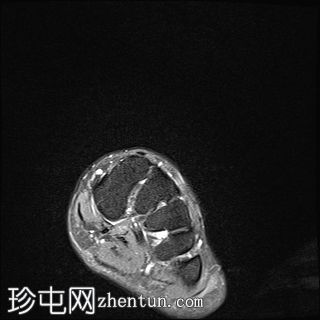

3.jpg

轴向PD

脂肪饱和度

舟骨呈二分状,分为两个骨块——较大的内侧骨块和较小的外侧骨块。

内侧骨折块外侧面呈“逗号状”,舟骨相对于距骨头轻微向内移位。

外侧骨折块及其外侧均呈斑片状T1低信号和PD FS高信号,并伴有硬化和微小囊肿,提示软骨联合/纤维界面存在慢性应激反应或退行性改变,可能伴有缺血性坏死。

双分舟骨区域外未见急性骨折线或骨髓水肿。

周围跗骨和关节未见明显异常。

未见明显软组织异常或关节积液。